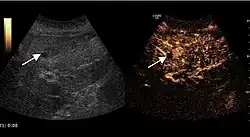

However, it is able to detect the appearance of new lesions and to assess the occurrence of any complications of disease progression (ascites or portal vein thrombosis). Color Doppler ultrasound can be useful sometimes being able to show the presence of intratumoral vasculature as a sign of incomplete therapy or intratumoral recurrence. The absence of Doppler signal does not exclude the presence of viable tumor tissue. CEUS exploration, by its ability to enhance intra-lesion microcirculation, has proved its utility in monitoring therapeutic efficacy. Its indications are defined for HCC ablative treatments (pre, intra and post-therapy), while monitoring of systemic therapies of HCC and metastases are not validated indications at this time, but with proved efficacy in extensive clinical trials (Claudon et al., 2008). CEUS examination cannot completely replace the other imaging diagnostic methods currently in use because of the known limitations of the ultrasound method (operator/ equipment dependent, ultrasound examination limitations). In addition to bloating, in cancer patients post-therapy steatosis occurs, which prevent deep visibility. Spiral CT scan remains the method of choice in monitoring cancer therapies because it provides an overview of tumor extension and it is not limited by bloating or steatosis.

2D ultrasound, Doppler ultrasound and especially CEUS can play an important role in pretherapeutic staging, particularly when sectional imaging investigations (CT, MRI) provide uncertain results or are contraindicated. During the interventional procedure, ultrasound allows guidance of the needle into the tumor. CEUS allows guidance in areas of viable tissue and avoids intratumoral necrotic areas. CEUS also allows assessment of therapeutic effect immediately post-procedure (with the possibility of reintervention in case of partial response) . To accurately assess the effectiveness of treatment it is mandatory to compare the tumor diameter before therapy with the ablation area. The volume of damaged tissue must be higher than the initial tumor volume. CEUS appearance is that of central nonenhanced area showing a peripheral homogeneous hyperenhanced rim due to post-procedure inflammation. 24 hours after the procedure the inflammatory peripheral rim is thinning and the necrotic area appears larger than at the previous examination. Thus, a possible residual tumor may appear more evident. Residual tumor has poorly defined edges, irregular shape, and the tumor diameter is unchanged. Residual tumor tissue is evidenced at the periphery of the tumor as an eccentric area behaving as the original tumor at CEUS examination, with arterial hyperenhancement and portal and late wash-out. Ultrasound examination 24 hours after the procedure, including CEUS, can show apart from the character of the lesion any potential post-intervention complications (e.g. active bleeding).

Local recurrence is defined as recurrence of a hyperenhanced area at tumor periphery in the arterial phase, with portal and late wash-out. Sometimes, especially for HCC treated by alcoholization (PEI) hyperenhanced septa or vessels can be shown inside the lesion.